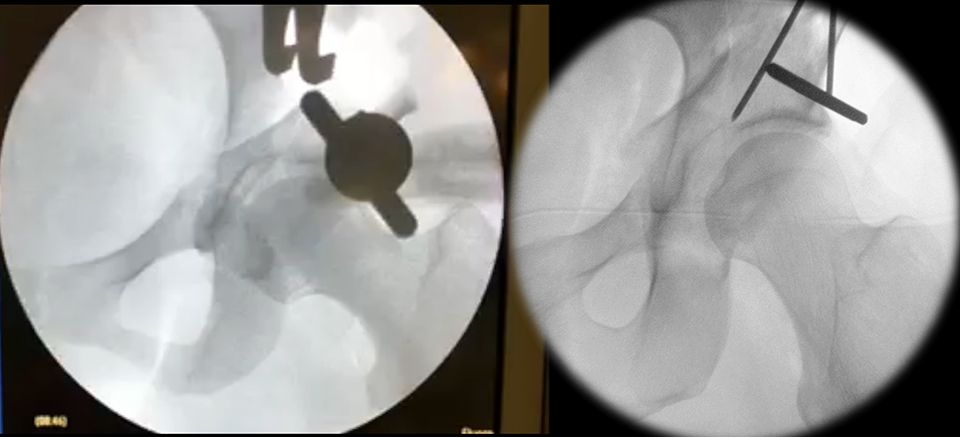

After these osteotomies the acetabular fragment should be careful mobilized with a laminar spreader and 1 Steinmann-pin (Fig. 15). Often there are still same bone brides between the ischium and the retroacetabular osteotomies. These bridges should be brocken with a curved osteotome which is placed under fluoroscopic control and after spreading the osteotomy with a laminar spreader. After all osteotomies are finished, acetabular reorientation remains a difficult step and care should be taken to achieve proper acetabular reorientation. The goal of reorientation is an LCE of 30°, a positive acetabular index and an anteverted acetabulum The reoriented acetabulum is then temporarily secured by two Kirschner wires that bridge the supraacetabular osteotomy (Fig. 15).

To avoid postoperative limitation in ROM or femoroacetabular impingement the freedom of motion after reorientation and before definite fixation of the acetabular fragment should be checked with minimum of 120° flexion and 30° internal rotation in 90° hip flexion. If an optimal acetabular reorientation and adequate ROM has been achieved the acetabular fragment is definitely fixed with four 4,5mm screws. The screw placement is verified with fluoroscopy to verify their extraarticular position (Fig. 16).